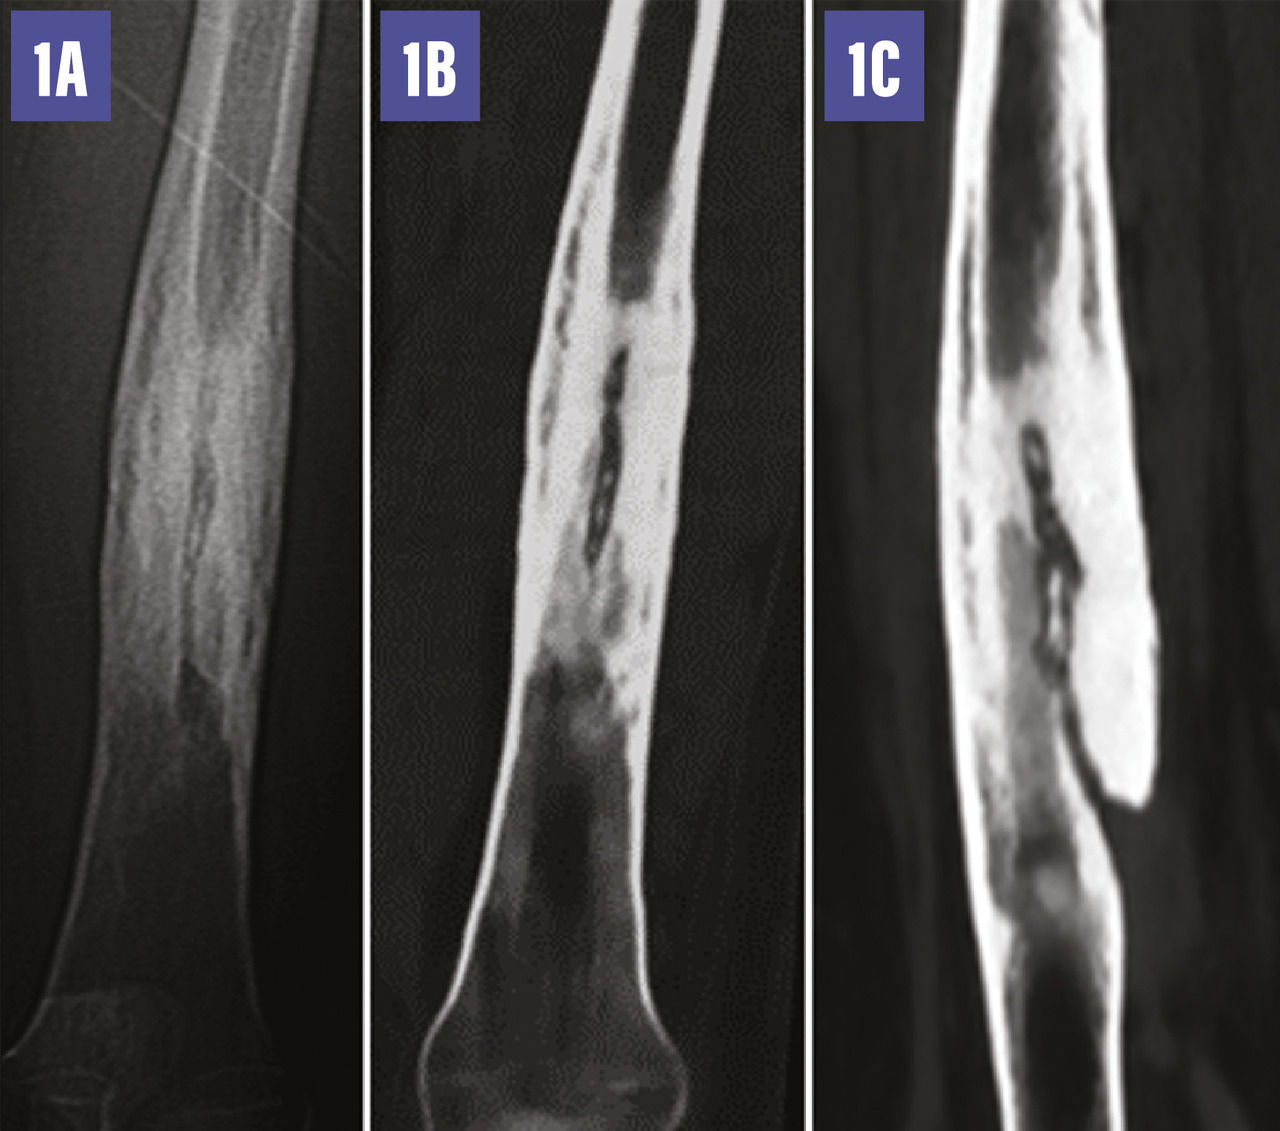

Une radiographie standard complétée par un scanner (fig. 1 ) met en évidence un épaississement cortico-périosté de la diaphyse fémorale, une condensation de l’os médullaire centrée par une ostéolyse linéaire décrivant un trajet fistuleux qui alimente une collection abcédée des parties molles renfermant des séquestres osseux (fig. 2 ). Le diagnostic d’ostéomyélite chronique est retenu.

L’imagerie radiologique standard montre un remodelage de l’os avec un épaississement cortical composé d’appositions périostées épaisses et irrégulières. Au sein de l’os, on observe des plages radiotransparentes dans lesquelles on peut retrouver un séquestre osseux. Le scanner et l’imagerie par résonance magnétique (IRM) permettent d’apprécier avec davantage de précision l’étendue de la maladie dans les tissus mous et la cavité médullaire, et représentent actuellement les examens de choix. Le scanner permet en particulier l’évaluation du cortex osseux, la recherche d’un séquestre osseux, un corps étranger ou une fistule. L’IRM permet de mieux apprécier les abcès ou collections.1,2